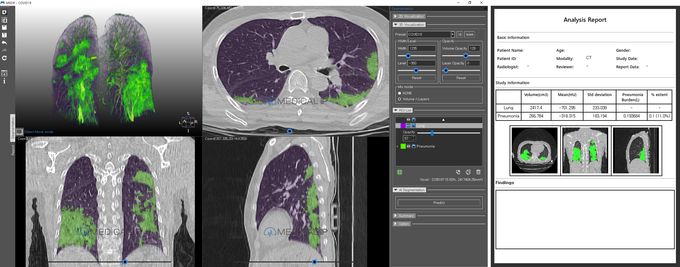

¼­¿ï´ë, Äڷγª19 CT ºÐ¼® ¼ÒÇÁÆ®¿þ¾î °³¹ß¡¤¹èÆ÷

µ¥Àϸ®¸Þµð ¹Ú´ëÁø ±âÀÚ] ¼­¿ï´ëÇб³º´¿ø ¿µ»óÀÇÇаú ÀÇ·áÁøÀÌ ±¹³» ´Ù±â°ü ¿¬±¸Áø°ú Çù·ÂÇØ Äڷγª19 CT ºÐ¼® ¼ÒÇÁÆ®¿þ¾î¸¦ °³¹ßÇϰí, À̸¦ Àü¼¼°è¿¡ ¹«·á·Î ¹èÆ÷Çß´Ù.

ÇØ´ç ¼ÒÇÁÆ®¿þ¾î´Â ÀΰøÁö´É(AI) ÀǷ῵»ó ºÐ¼® Ç÷§Æû ¹× ÀÇ·á¿ë 3DÇÁ¸°ÆÃ Àü¹®±â¾÷ÀÌÀÚ ¼­¿ï´ëº´¿ø ½ºÇÉ¿ÀÇÁ º¥Ã³È¸»çÀÎ ¸ÞµðÄþÆÀÌÇÇÀÇ ±â¼úÀ» ±â¹ÝÀ¸·Î °³¹ßµÆ´Ù.

¸ÞµðÄþÆÀÌÇÇ´Â CT, MRI µî 2Â÷¿ø ÀǷ῵»óÀ» 3Â÷¿øÀ¸·Î Áï°¢ ±¸ÇöÇϰí À̸¦ ºÐÇÒ ¹× ºÐ¼®ÇÒ ¼ö ÀÖ´Â ¿øÃµ±â¼úÀ» º¸À¯Çϰí ÀÖ´Ù.

¼ÒÇÁÆ®¿þ¾î´Â ¸ÞµðÄþÆÀÌÇÇ È¨ÆäÀÌÁö¸¦ ÅëÇØ ¹«·á·Î ´Ù¿î·Îµå ¹ÞÀ» ¼ö ÀÖÀ¸¸ç, Äڷγª19 ȯÀÚÀÇ CT ¿µ»óÀ» ºÐ¼®ÇØ 1ºÐ ³»¿Ü·Î Äڷγª Æó·ÅÀ» ÀÚµ¿À¸·Î ŽÁö, ºÐÇÒ, Á¤·®È­ÇÑ´Ù.

À̸¦ ÅëÇØ Æó·ÅÀÌ ½ÉÇÑ ÁßÁõȯÀÚ ¼±º°°ú ¸ð´ÏÅ͸µ¿¡ ±â¿©ÇÒ °ÍÀ¸·Î ±â´ëµÈ´Ù.